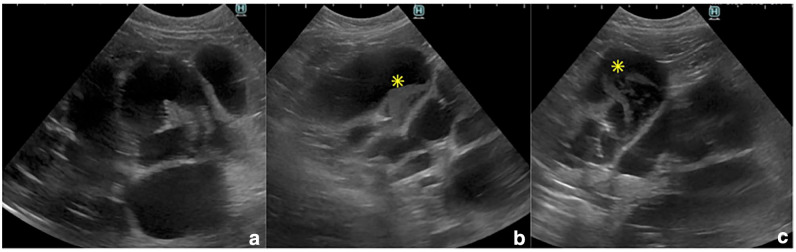

Case summary: An 8-year-old castrated male mixed-breed cat was presented with recurrent vomiting, weight loss and abdominal distension. Blood work revealed hyperbilirubinaemia and elevated liver enzyme activities. Abdominal ultrasound and CT showed marked dilation and obstruction of the common bile duct (CBD) due to chronic cholecystitis and cholangiohepatitis. The cat was diagnosed with CBD obstruction secondary to chronic cholecystitis and cholangiohepatitis and was initially treated with antibiotics and prednisolone. Surgical intervention was performed because of complete CBD obstruction and worsening icterus that was unresponsive to medical management. A choledochoduodenostomy was performed using a simple side-to-side anastomosis between the CBD and the duodenum. The patient recovered uneventfully after surgery without significant complications. At the last follow-up, 6 months postoperatively, the cat remained clinically stable.